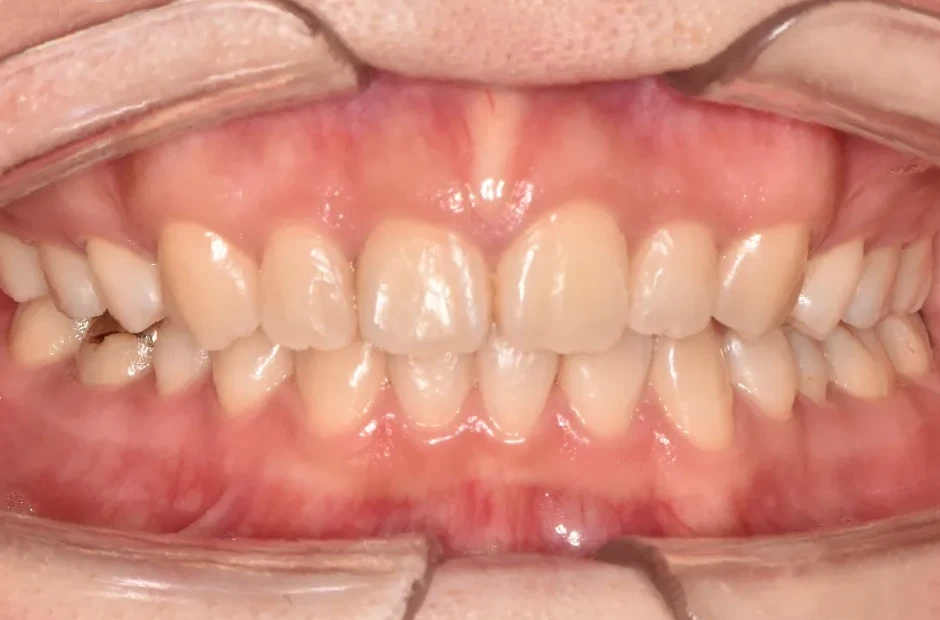

反対咬合

| 診断名・主訴 | 下顎前突、叢生 |

| 年齢・性別 | 23歳・女性 |

| 治療期間・回数 | 3年 |

| 治療に用いた主な装置 | 上顎5,5 下顎4,4 |

| 抜歯部位 | 舌側矯正 |

| 治療費 | 100万円(税抜) |

| リスク・副作用 | 装置による違和感・疼痛・歯肉退縮・歯根吸収・虫歯のリスクなど |

治療前